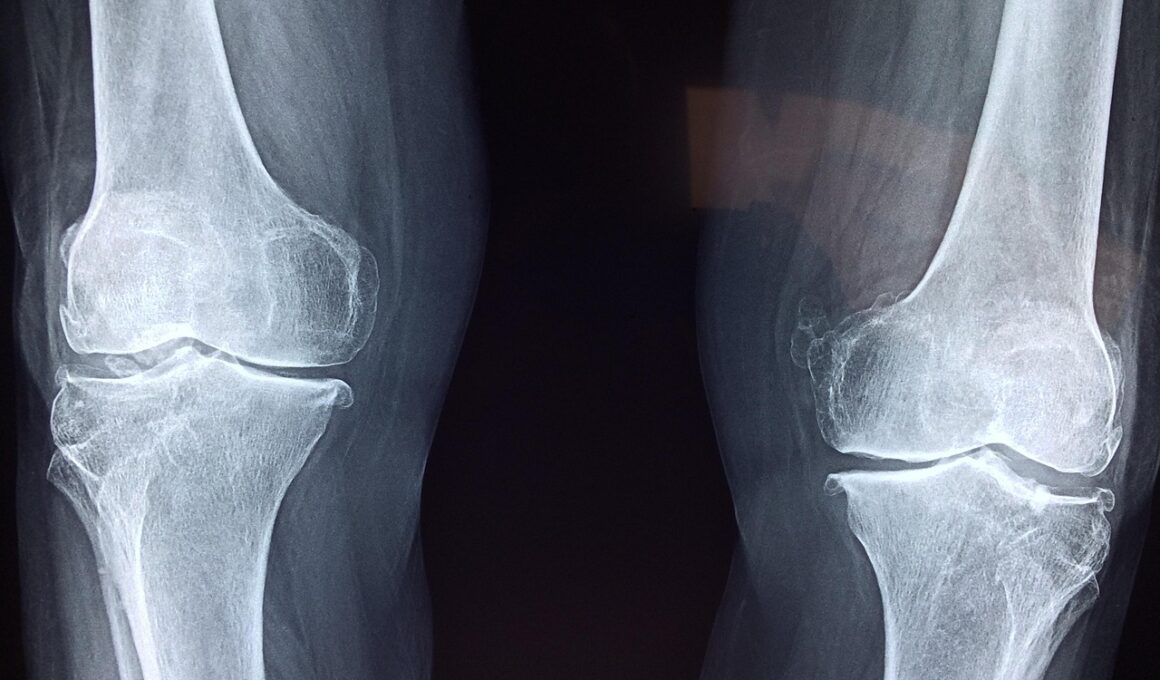

Joint health is vital for maintaining overall physical activity and quality of life. Isometric exercises, characterized by muscle tension without movement, directly benefit joint health. By engaging various muscle groups, these exercises provide stability and support for the joints, reducing the likelihood of injury during more dynamic movements. Moreover, isometric training strengthens the ligaments and tendons surrounding joints, contributing to a robust musculoskeletal system. This approach can be particularly beneficial for individuals recovering from injuries, as it allows them to build strength without compromising joint integrity. For beginners, starting with fundamental isometric holds, such as the plank or wall sit, can yield quick results. As strength develops, these exercises can be progressed by increasing hold durations or adding variations to target specific areas. Regularly integrating isometrics into a workout program not only enhances strength but also improves endurance and flexibility. Additionally, these exercises can be performed anywhere, making them incredibly convenient. Being consistent is crucial; weekly sessions yield better results. Ultimately, embracing isometrics can lead to improved joint function, enhanced mobility, and a lower risk of injury.

Another crucial aspect of isometric training is its role in preventing injuries. By strengthening the muscles around the joints, individuals create a more supportive structure that can better withstand stress. This is especially important for athletes, where injuries can sideline performance for extended periods. Through consistent isometric training, individuals can improve muscular endurance, further enhancing their ability to perform dynamic movements safely. These exercises can develop stability in various positions, including static holds that mimic functional postures athletes encounter in their sports. Moreover, the mental aspect of isometric training, where focus combines physical effort, contributes to a more profound mind-body connection. This awareness aids in preventing injuries related to poor body mechanics. Engaging multiple muscle groups simultaneously can lead to balanced strength distribution, avoiding muscular imbalances that often lead to injuries. Whether one is lifting weights or performing daily tasks, strength gained from isometrics supports a body better prepared for various physical challenges. Ultimately, isometrics empower athletes and active individuals alike to enhance purposeful movement while mitigating injury risk effectively.